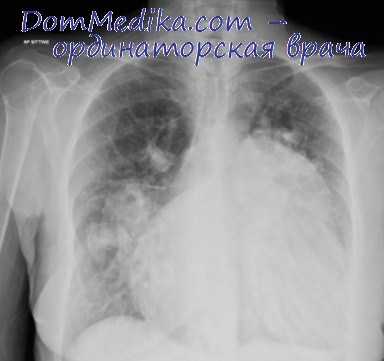

6. Рентгенологические данные: увеличение и усиление пульсации легочных корней, а также периферических легочных артерий («танец корней») или симптом Danelius. Более или менее выраженная пращевидная форма легочной дуги. Сердце несколько увеличено с закругленной верхушкой.

Рентгеноскопия легких обнаруживает выпячивание ствола легочной артерии, пульсацию корней и шаровидную форму сердца. ЭКГ-изменения характеризуются увеличением зубца Р во II и III стандартных отведениях и признаками гипертрофии правого желудочка.